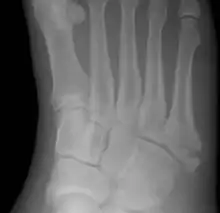

Pseudo-Jones fracture

For several reasons, a Jones fracture may not unite. The diaphyseal bone (zone II), where the fracture occurs, is an area of potentially poor blood supply, existing in a watershed area between two blood supplies. This may compromise healing. In addition, there are various tendons, including the fibularis brevis and fibularis tertius, and two small muscles attached to the bone. These may pull the fracture apart and prevent healing.

Zones I and III have been associated with relatively guaranteed union and this union has taken place with only limited restriction of activity combined with early immobilization. On the other hand, zone II has been associated with either delayed or non-union and, consequently, it has been generally agreed that fractures in this area should be considered for some form of internal immobilization, such as internal screw fixation.

These zones can be identified anatomically and on x-ray adding to the clinical usefulness of this classification.[21] Surgical intervention is not, by itself, a guarantee of cure and has its own complication rate. Other reviews of the literature have concluded that conservative, non-operative, treatment is an acceptable option for the non-athlete.[22]